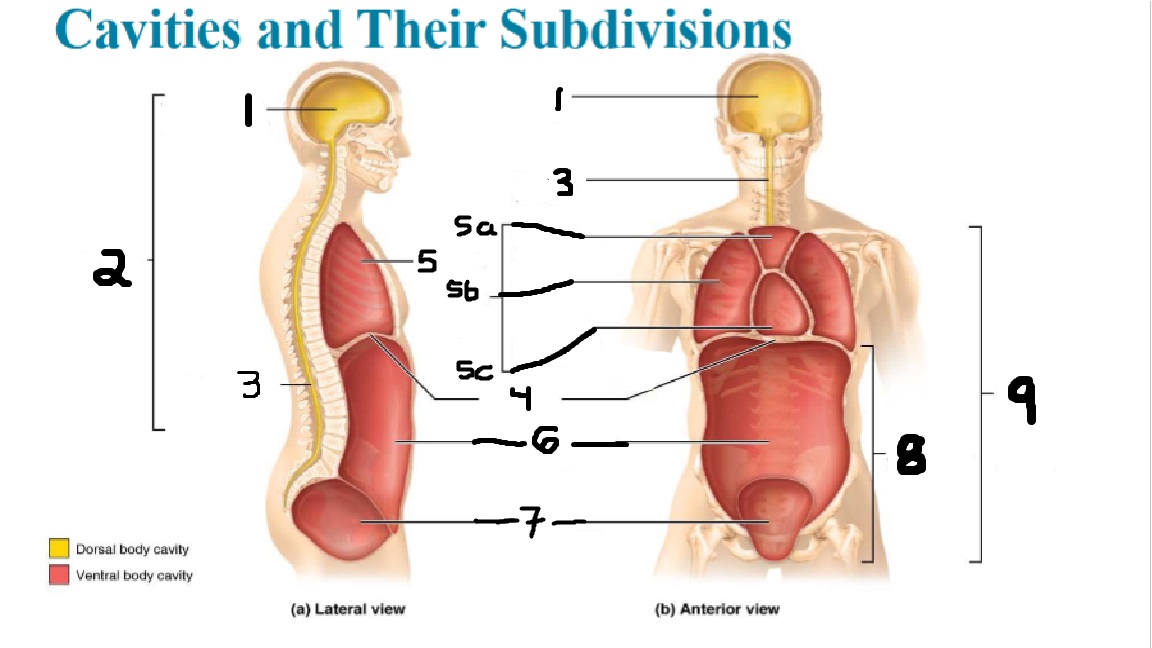

What cavities are part of the dorsal cavity?

The cranial and the Spinal (vertebral) cavities

What kind of cavity is labeled 2?

The dorsal body cavity (containing the cranial and spinal cavities)

What is the purpose of the dorsal cavity?

protects the nervous system

What is the main organ encased by the cranial cavity?

the brain

What cavity is labeled #1?

The cranial cavity

What is the main organ encased by the vertebral cavity?

the spinal cord

What is another word for the vertebral cavity?

the spinal cavity, or the spinal canal

What body cavity is labeled 3?

the vertebral cavity.

What cavities are included in the ventral cavity?

the thoracic, abdominal, and pelvic cavities.

What body cavity is labeled #6?

the abdominal cavity.

What are the main organs of the abdominal cavity?

the digestive organs such as the stomach, intestines, spleen and liver

What cavities are included in the Abdominopelvic cavity?

the abdominal cavity and the pelvic cavity

What body cavity is labeled #8?

The Abdominopelvic cavity

What does the diaphragm separate?

the thoracic and the abdominal cavities

What is labeled #4?

the diaphragm

What organs does the pelvic body cavity contain?

urinary/reproductive organs and rectum

What is labeled #7?

the pelvic cavity

What does the thoracic cavity encase?

the heart and the lungs

What is labeled #5?

the thoracic cavity

What part of the thoracic body cavity is labeled 5a?

superior mediastinum

What part of the thoracic body cavity is labeled 5b?

pleural cavity

What part of the thoracic body cavity is labeled 5c?

pericardial cavity within the mediastinum

What body cavity encloses the heart?

the pericardial cavity.